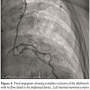

Case Report. A 64-year-old patient with multiple cardiovascular risk factors with unstable angina and severe ostial and proximal left anterior descending coronary artery (LAD) disease with a distal left main coronary artery plaque underwent coronary artery bypass graft (CABG) with LIMA graft to the LAD in 2004. Following the surgery, he continued to have mild exertional angina, which was controlled on medical therapy. He now presented with increasing angina over the last 6 months. The patient underwent a myocardial perfusion imaging study (SPECT), which revealed an extensive area of ischemia in the LAD territory. Coronary angiography revealed a patent LIMA-

LAD graft with no evidence of progression of the native lesions. However, there was a large intercostal branch measuring 2.5 mm (almost the same size as the LIMA itself) arising from the proximal segment of the LIMA. On the basis of these findings, a diagnosis of coronary steal syndrome due to the large unligated sidebranch of the LIMA (Figure 1) was made. After discussion with the patient and the cardiac surgeons, a consensus decision to close the sidebranch was reached.

Angiography confirmed excellent device position and complete occlusion of blood flow distal to the device with improvement of flow in the LIMA graft and LIMA-LAD flow (Figure 2). Following the procedure, the patient had complete resolution of his symptoms.